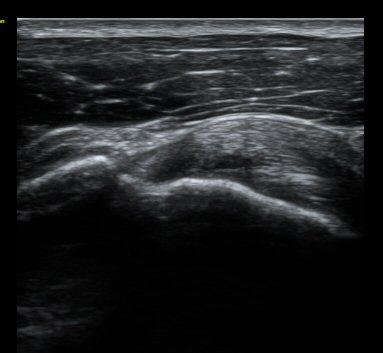

±Ø»ó°Ç Á¾´Ü¸é°Ë»ç¿Í Ⱦ´Ü¸é°Ë»ç¿¡¼­ ±Ø»ó°Ç³» ¹Ì¼¼ÇÑ °£±ØÀÌ °üÂûµÊ(±×¸² 6, 7, 8).

°ßºÀ ¿ÜÃø¿¡ ŽÃËÀÚ¸¦ ´ë°í ½ÃÇàÇÑ Ãæµ¹°Ë»ç¿¡¼­ °ßºÀ ¿ÜÃø¿¡ ¼ö¾×Àú·ù°¡ °üÂûµÇ¾ú´Ù.(±×¸² 9).